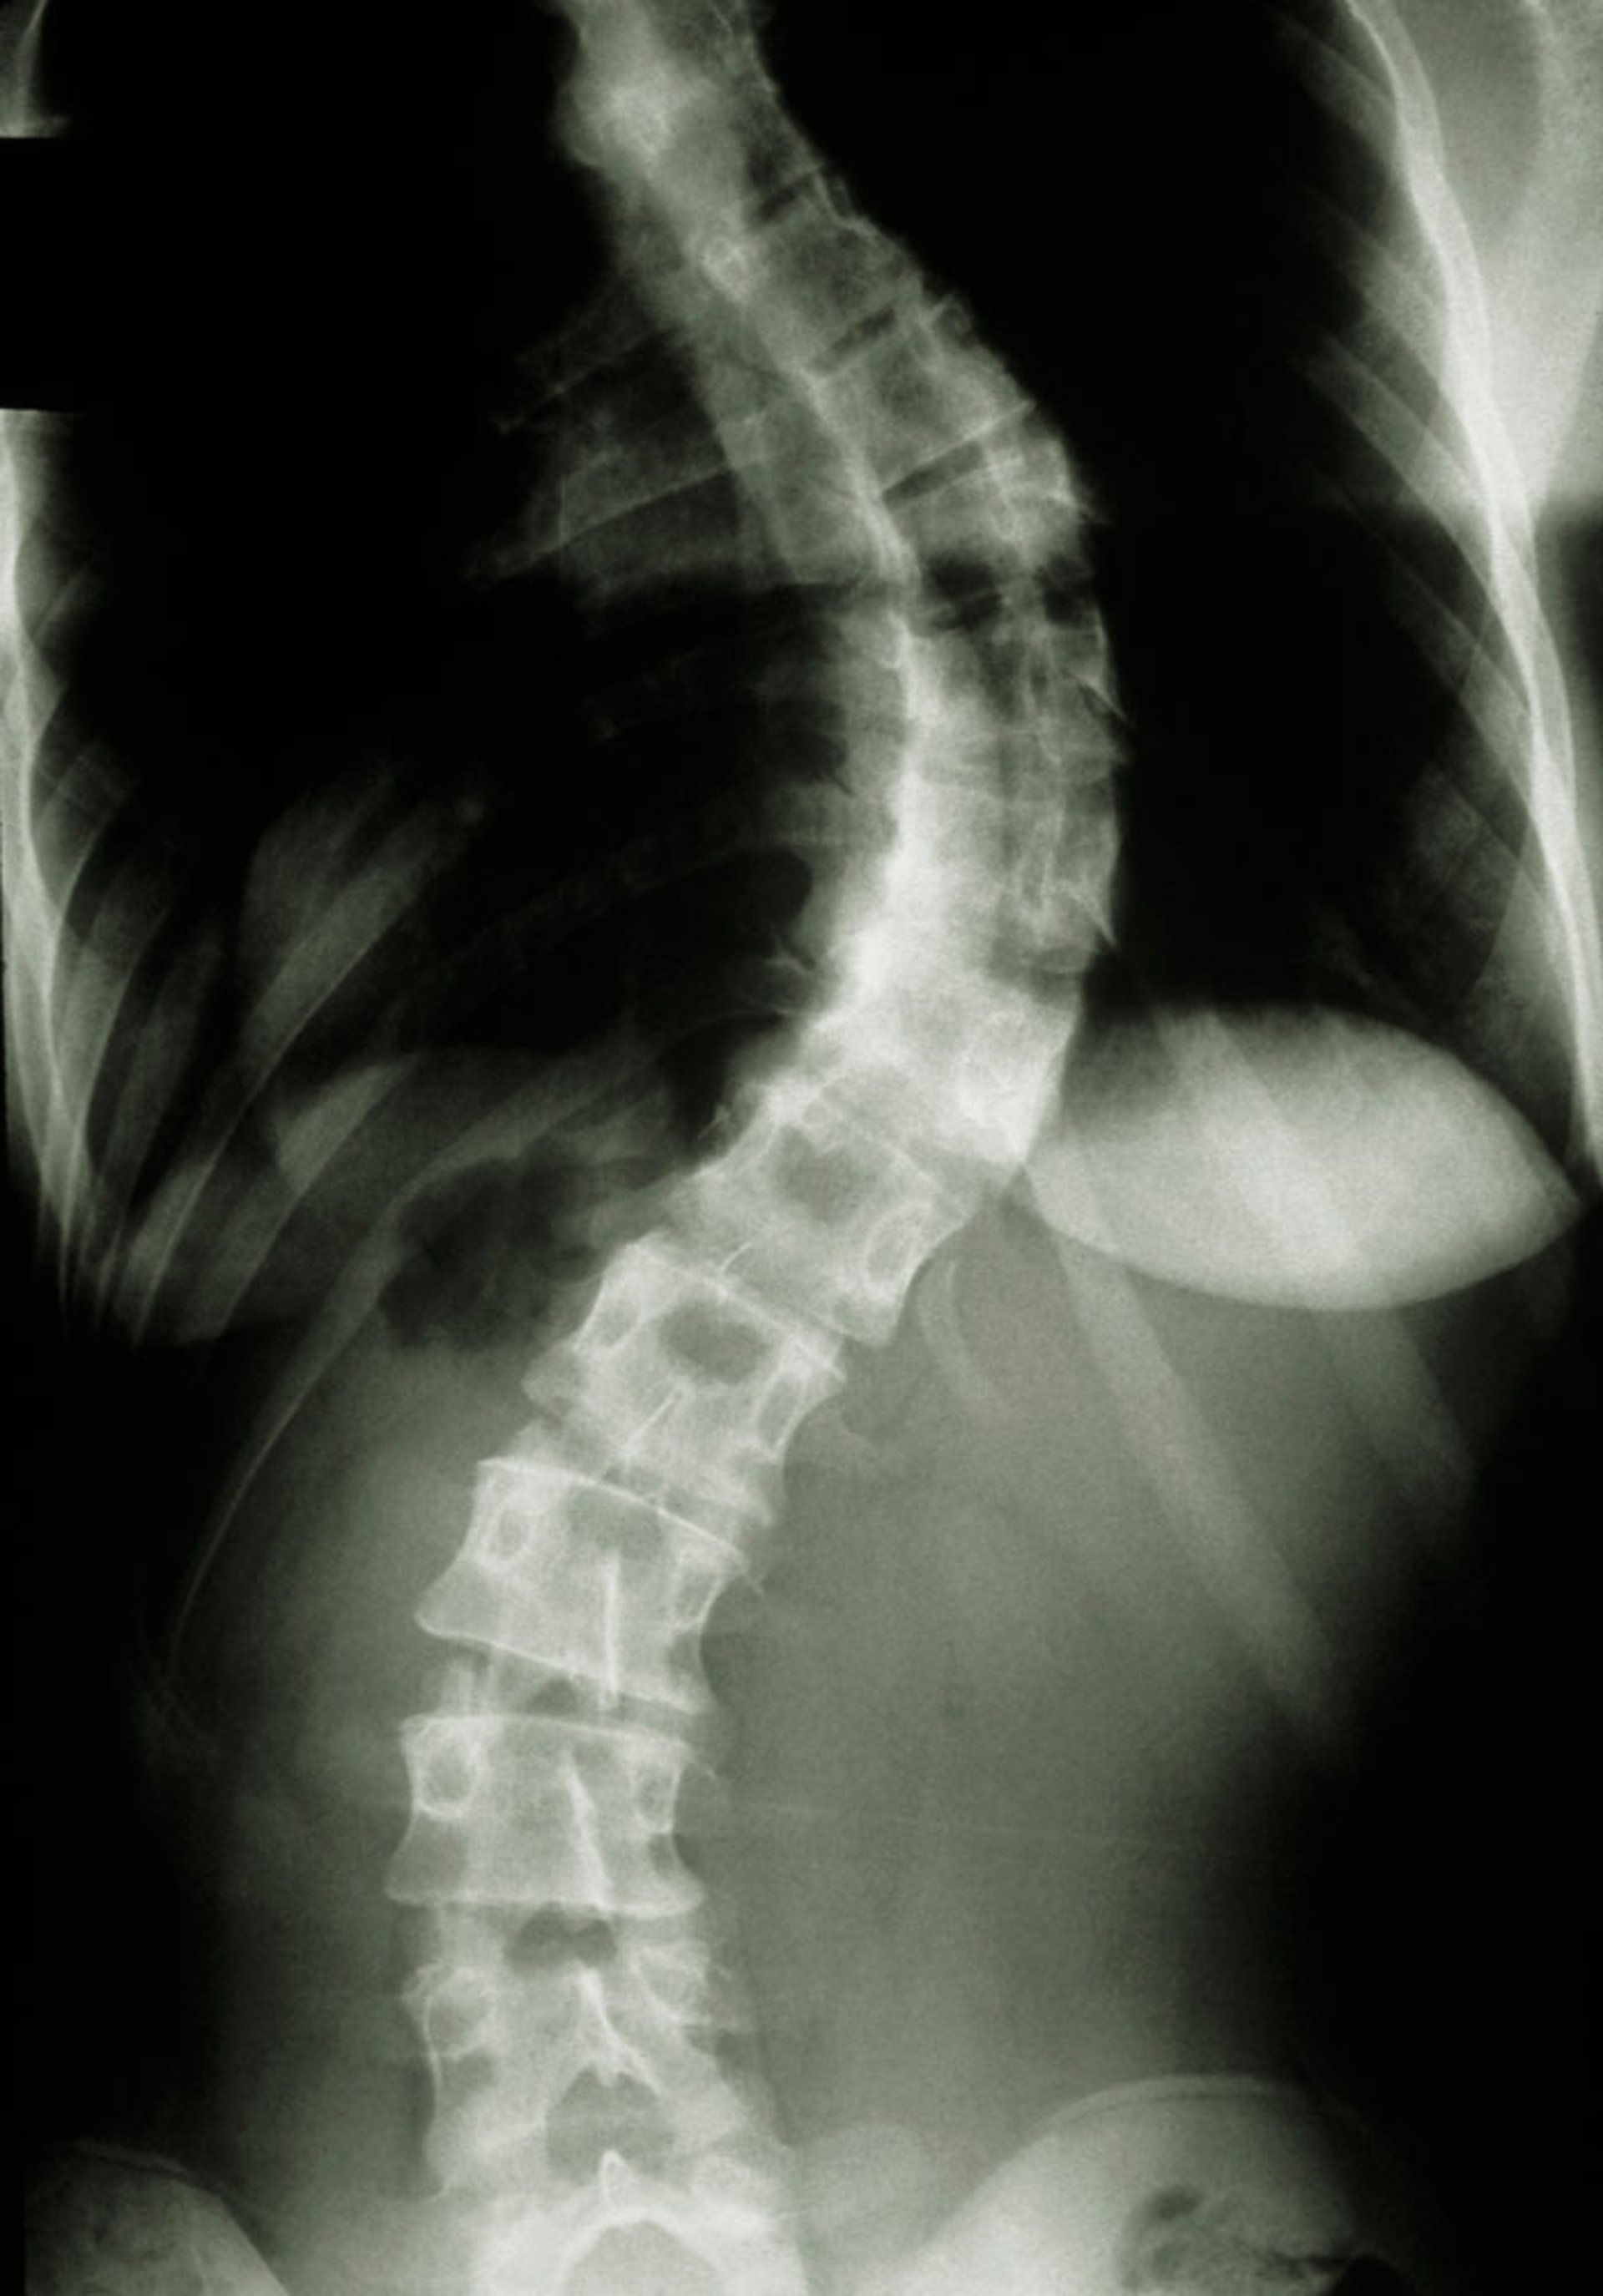

脊柱侧弯(脊柱 X 光片)

MEDICAL PHOTO NHS LOTHIAN/SCIENCE PHOTO LIBRARY

特发性脊柱侧凸